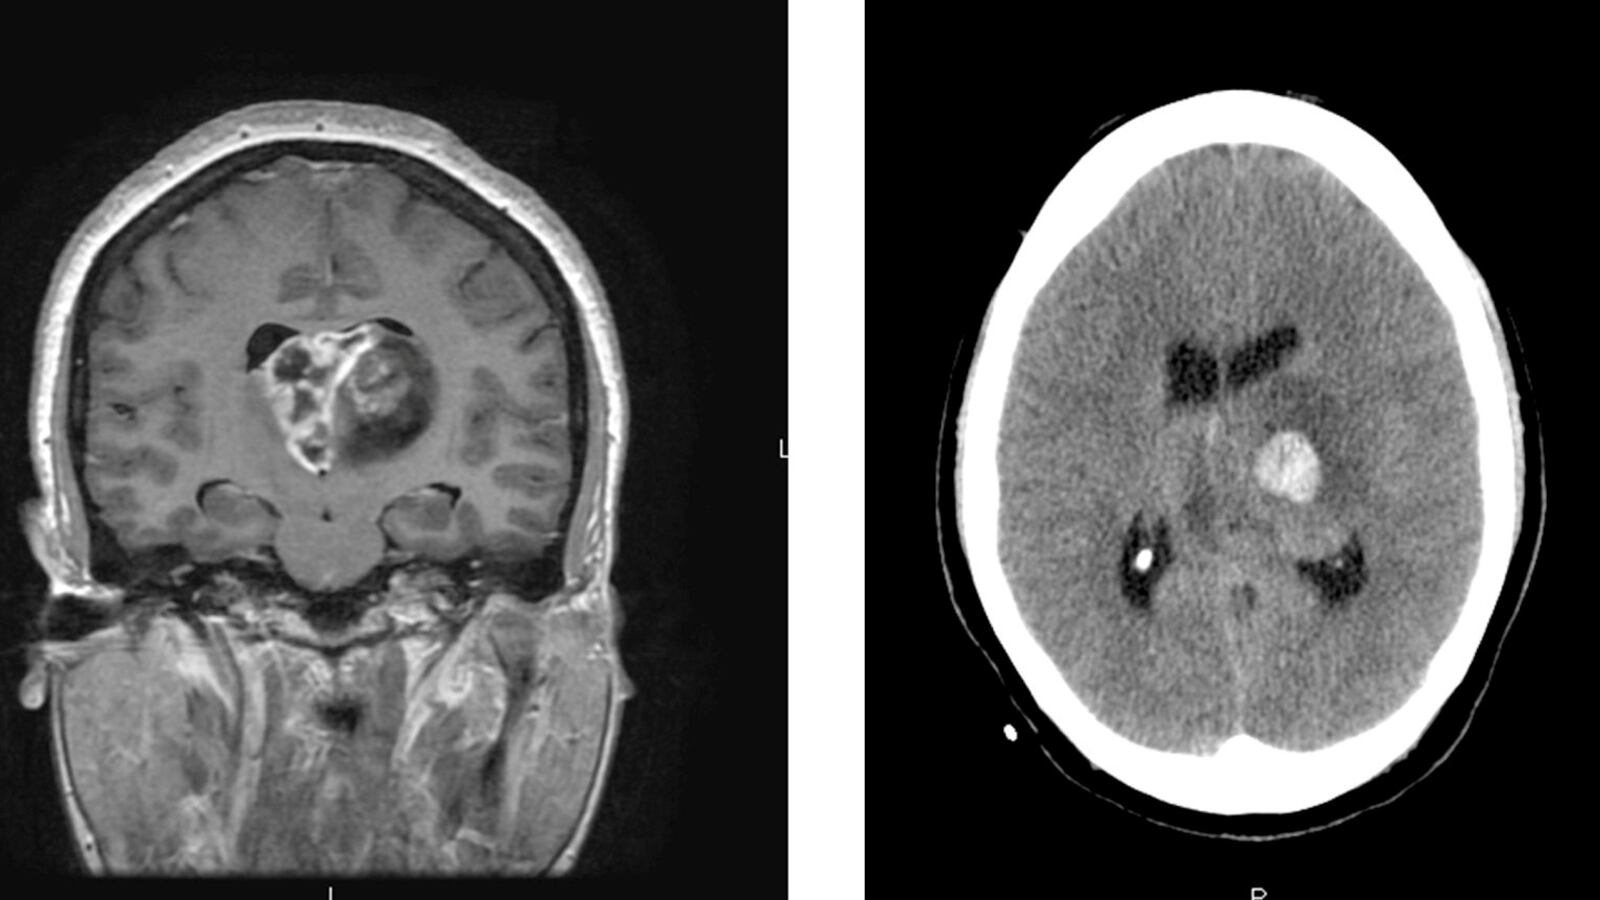

Over the last eight years, the pharmaceutical company NextSource has hiked the price of a drug for brain cancer patients from $50 to $1,000 a pill, even though the patent for it is expired. Now, according to The Wall Street Journal, the company is dropping out of a program for Medicare patients that made Gleostine more affordable. NextSource did not explain its decision and says patients can ask the company for financial assistance. But experts say it’s a blow to those with glioblastoma and some other brain cancers. “The problem is that patients with this terrible tumor now no longer have easy access to one of the few approved chemotherapies,” Dr. Patrick Wen of the Dana-Farber Cancer Institute in Boston told the Journal.